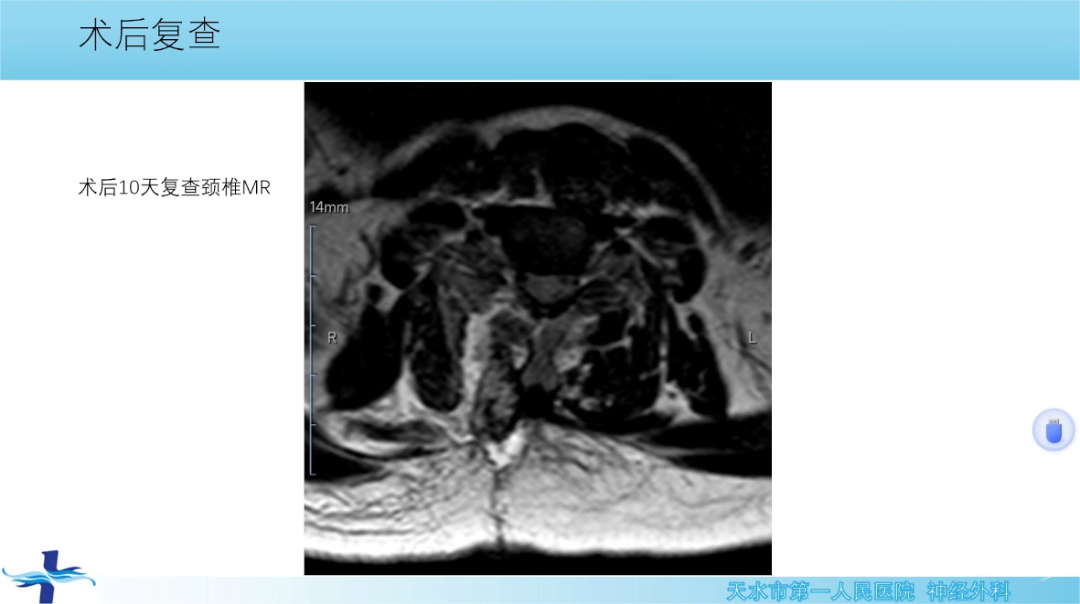

讲题:旁正中切口一侧半椎板入路治疗椎管内病变